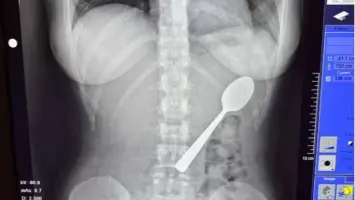

بلجيكية تبتلع ملعقة عن طريق الخطأ.. تفاصيل الحادثة

في حادثة غريبة أثارت دهشة الكثيرين، اضطرت بلجيكية تبلغ من العمر 28 عاماً للخضوع لعملية طبية بسيطة لإخراج ملعقة ابتلعتها .